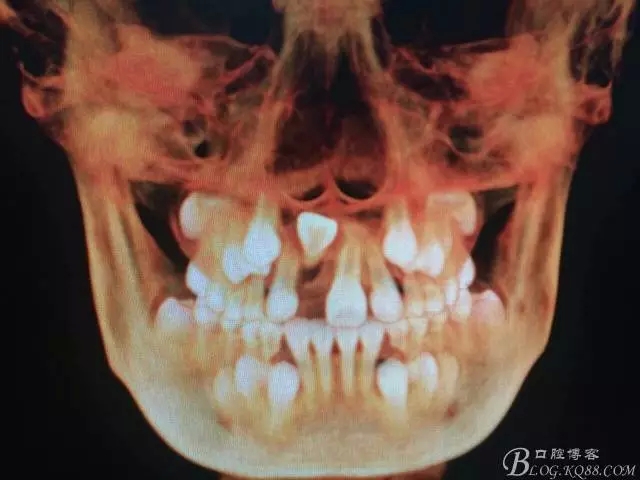

圖3.右上11的三維影像位置。